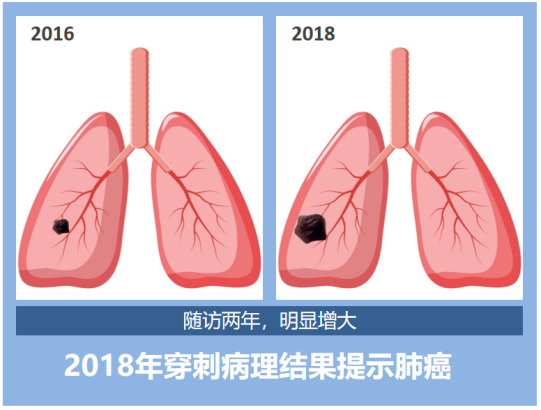

这是大家最关心的事了,我们来看几组肺结节随访病例模式图。

第一组:实性结节

患者3:2016年右肺发现一枚实性肺结节,两年后复查CT,这枚结节明显增大,形态逐渐不规则,最后病理结果提示为肺癌。